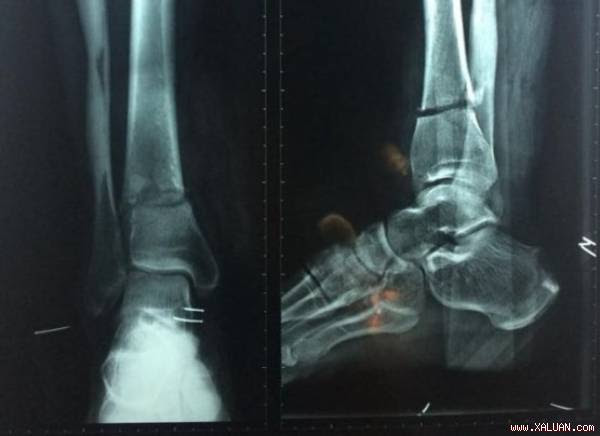

Bác sĩ đã nối phần chân gần đứt lìa của ông Châu sau khi nạn nhân bị lưỡi dao máy cắt cỏ chém vào chân.

Bác sĩ chẩn đoán chân phải ông Châu bị đứt động mạch và thần kinh chày sau, đứt toàn bộ gân cơ mặt sau. Ê-kíp rửa vết thương, cắt lọc phần dập nát và thực hiện vi phẫu nối động mạch, thần kinh.

Sau phẫu thuật, phần chân suýt đứt liền đã hồng hào trở lại. Bác sĩ Khánh cho biết, những tai nạn đứt chân do máy cắt cỏ không hiếm gặp, vì thế người cắt cỏ cần mang giày ống cao và dày để bảo vệ.